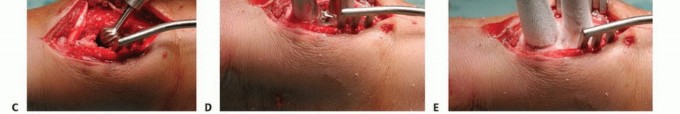

تقنية الصب المباشر بالنيتروجين السائل تفاصيل الإجراء

تعتبر تقنية الصب المباشر بالنيتروجين السائل (Direct Pouring Liquid Nitrogen Technique) في العلاج بالتبريد لأورام العظام من التقنيات المتقدمة التي تتطلب دقة عالية وخبرة جراحية متخصصة. يفضل الأستاذ الدكتور محمد هطيف هذه التقنية نظرًا لفعاليتها في تحقيق تجميد عميق وشامل للورم، مع الحفاظ على الأنسجة السليمة المحيطة.

التحضير قبل الإجراء

- التقييم الشامل: يقوم الدكتور هطيف بإجراء تقييم سريري دقيق، ومراجعة التاريخ المرضي للمريض، وإجراء الفحوصات التصويرية اللازمة (الأشعة السينية، الرنين المغناطيسي، الأشعة المقطعية، ومسح العظام) لتحديد حجم الورم وموقعه وعلاقته بالهياكل الحيوية المحيطة.

- الخزعة (Biopsy): في معظم الحالات، يتم أخذ خزعة من الورم لتأكيد التشخيص النسيجي وتحديد ما إذا كان حميدًا أو خبيثًا.

- المناقشة مع المريض: يشرح الدكتور هطيف الإجراء بالتفصيل للمريض وذويه، ويناقش الفوائد والمخاطر المحتملة